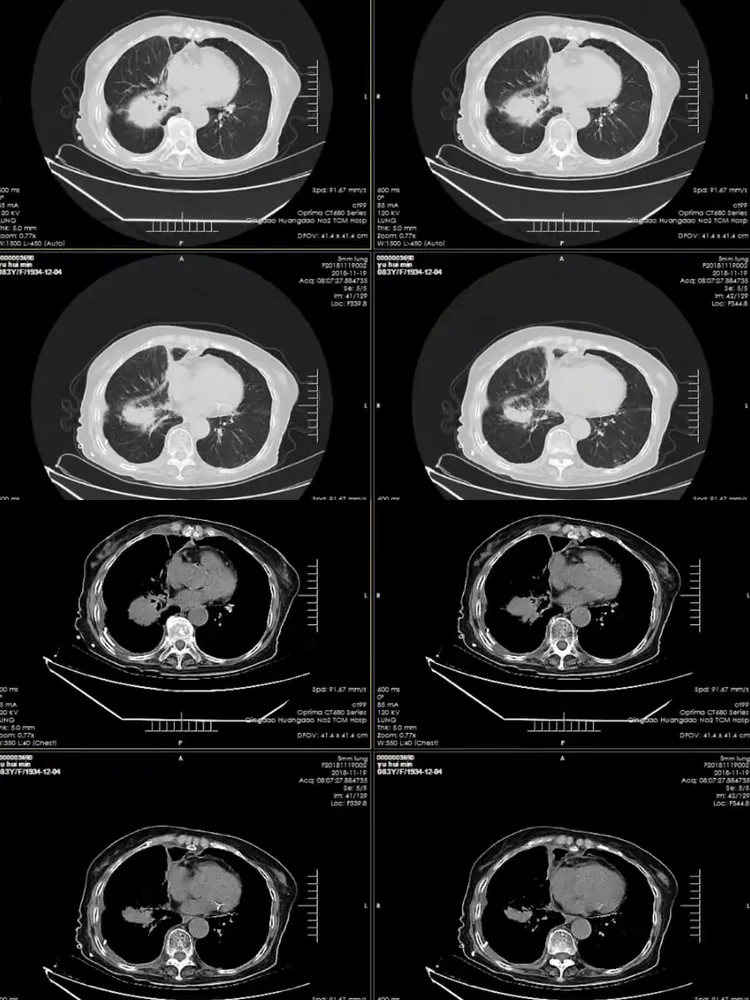

这个月的复查结果糟透了,肺上肿瘤疯长,已经发生了一次咳血。现在没有[s0]射波刀后肿瘤会消失吗[s1]是不是做了肺部穿刺就一定是肺肿瘤或者肺癌?[s2]图片[s3]肺上长肿瘤严重吗 小红书[s4]肺上良性肿瘤怎么办才能消除[s5]确诊为肺癌晚期。医生告知王阿姨,肿瘤发展较快,手术治疗的机会不大。[s6]后,医生的诊断结果让所有人震惊——是肺部恶性肿瘤,且已经是晚期了。[s7]右肺尖肿瘤,16个月迅速长大[s8]吸烟30年,虽已戒烟5年,但这个患者的肺黑得吓人,肺上的恶性肿瘤更加触目惊心![s9]岳母肺部肿瘤病情演变[s10]肺部肿瘤[s11]新方法可能减少肺部肿瘤的生长[s12]微信图片_20190404112215.jpg[s13]胸部肿瘤综合治疗之一肺癌篇~~~科大二附院胸外科胡举副主任医师治疗体会[s14]考虑肺部肿瘤[s15]肺部的恶性肿瘤[s16]肺部肿瘤[s17]右肺上叶肿瘤,穿刺难度大,患者高龄基础疾病多,手术中并发症风险大。[s18]麻烦给看一下我的肺部有肿瘤吗?谢谢了?[s19]肺上肿瘤切除手术好做吗(肺部肿瘤位置尴尬)(1)[s20]肺部巨大肿瘤[s21]少见!6厘米巨大肺部肿瘤—兖矿新里程总医微创切除![s22]查发现患者肺部也有一个肿瘤,考虑患者原发肿瘤在肺部,脑部是转移瘤。[s23]右肺上叶贴水平裂的肿瘤,手术切除范围的考量(病例回顾)[s24]肺部长肿瘤的症状[s25]这是一名35岁女性,左肺上叶将近4厘米的肿物,没有任何症状,查体时才发现,4厘米的肿瘤都没有临床症状,还是很可怕的。腔镜下切除,淋巴结应该不至于有转移,还是略偏早期,但术后是需要靶向药物治疗或者化疗的,尽量降低复发概率。所以,肿瘤不能等有了症状再就诊,分期晚了医生也没有办法。[s26]以前照片[s27]患者高龄基础疾病多,手术中并发症风险大。术前ct见右上肺肿瘤术中操作[s28]肺肿瘤影像大汇总,看完深刻理解[s29]发展,甚至肺上的肿瘤已经缩小了百分之四十,于是在2019年1月3日出院了。在进行了四个疗程的治疗后,[s30]肺上长肿瘤严重吗 mip.haodf.com[s31]肺上长肿瘤严重吗 来自网易[s32]右肺尖肿瘤,16个月迅速长大[s33]肺肿瘤有哪些危害[s34]肺肿瘤[s35]肿瘤标记物虽然是正常的,但是咳嗽原因不明,ct却发现肺上长了肿物.[s36]肺部恶性肿瘤需要手术吗能治好吗[s37]肺上长了肿瘤必须要做穿刺检查吗?[s38]肺部肿瘤能治好吗[s39]